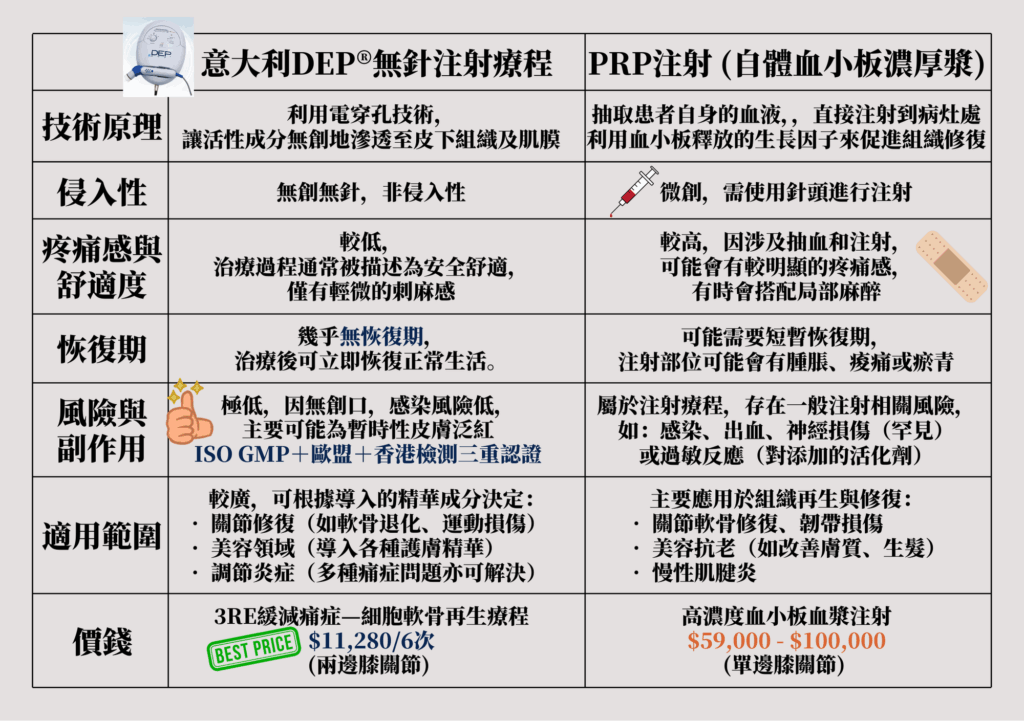

📊 DEP®無針療程 vs 傳統PRP注射 全面比較

| 比較項目 | 意大利DEP®無針注射療程 | 傳統PRP注射(自體血小板) |

|---|---|---|

| 技術原理 | 電穿孔無創導入活性成分,直達深層組織 | 抽血離心後注射血小板生長因子 |

| 侵入性 | 無創無針,非侵入性 | 微創,需抽血與針頭注射 |

| 疼痛感 | 輕微刺麻感,無明顯痛楚 | 較高,可能需局部麻醉 |

| 恢復期 | 幾乎無恢復期,治療後即可正常活動 | 需數天恢復,可能伴隨腫脹、瘀青 |

| 風險副作用 | 極低,僅可能暫時性皮膚泛紅 | 感染、出血、神經損傷等注射相關風險 |

| 適用範圍 | 關節修復、軟骨再生、炎症調節、美容護膚 | 主要用於組織再生,如軟骨與韌帶修復 |

| 價格(參考) | $11,280 / 6次(兩邊膝關節) | $59,000 – $100,000(單邊膝關節) |